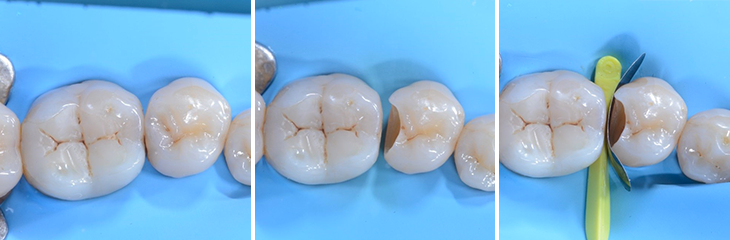

3. Cavité après préparation, nettoyage, élimination de la carie et désinfection.